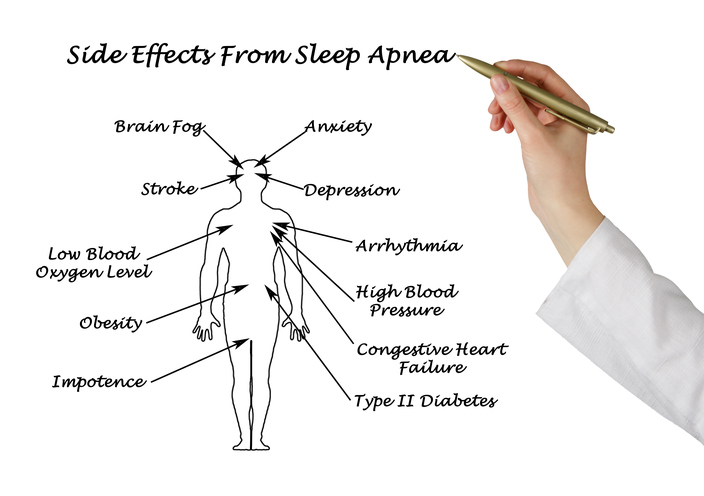

A hypertensive crisis is a quick and severe risk in blood pressure that can lead to a stroke. Extremely high blood pressure refers to readings of 180/120 mm Hg and higher and it can cause damage to the blood vessels. When blood pressure is this high, the heart is unable to pump blood efficiently. For ...click here to read more